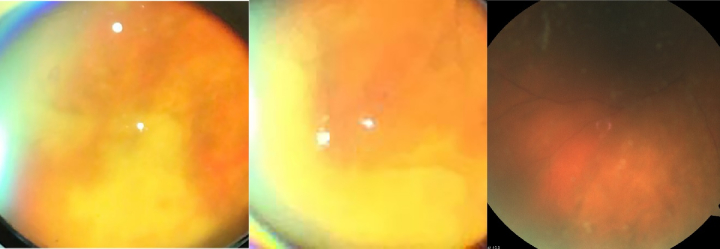

Case report: A 58-year-old female presented to our emergency department with sudden unilateral visual loss following a recent hospitalization for viral meningoencephalitis. Magnetic resonance imaging (MRI), cerebrospinal fluid (CSF) analysis, polymerase chain reaction (PCR) of the aqueous humor, reverse transcription polymerase chain reaction (RT-PCR) of the nasopharyngeal swab specimen, chest computed tomography (CT), and fundus photography were performed for the patient. Ophthalmic examination revealed severe ocular inflammation and yellowish patches of necrotizing retinitis in the right eye, compatible with the diagnosis of ARN. The result of aqueous humor PCR was positive for varicella zoster virus (VZV). The patient received a single intravitreal ganciclovir injection and 10 days of intravenous ganciclovir, followed by oral acyclovir. The patient underwent COVID-19 screening tests: while the chest CT scan showed features highly suggestive of COVID-19, the RT-PCR was negative on two occasions. Two months later, best-corrected visual acuity improved to 20/70 in the right eye, the anterior chamber reaction and keratic precipitates resolved, and the vitreous haze decreased significantly.